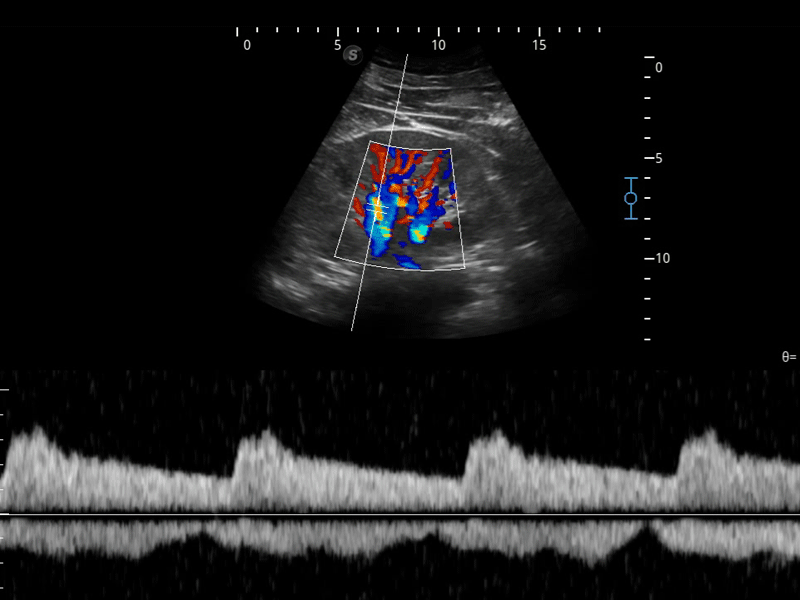

开立医疗通过不断的技术创新,为大众的生命健康提供持续关爱。P12 Plus采用全新一代超声成像平台,新平台旨在将真实还原组织解剖结构作为首要目标。平台采用全新集成化硬件模块,搭载新一代芯片,系统性能得到大幅提升,为您的诊断提供了丰富的临床信息。优异的图像表现,丰富的探头配置,全面的应用功能,为您日常诊断提供了可靠的助手。

凭借开立医疗先进的成像技术和优异的探头技术提供的清晰的图像表现,您可以更自信地做出临床决策。